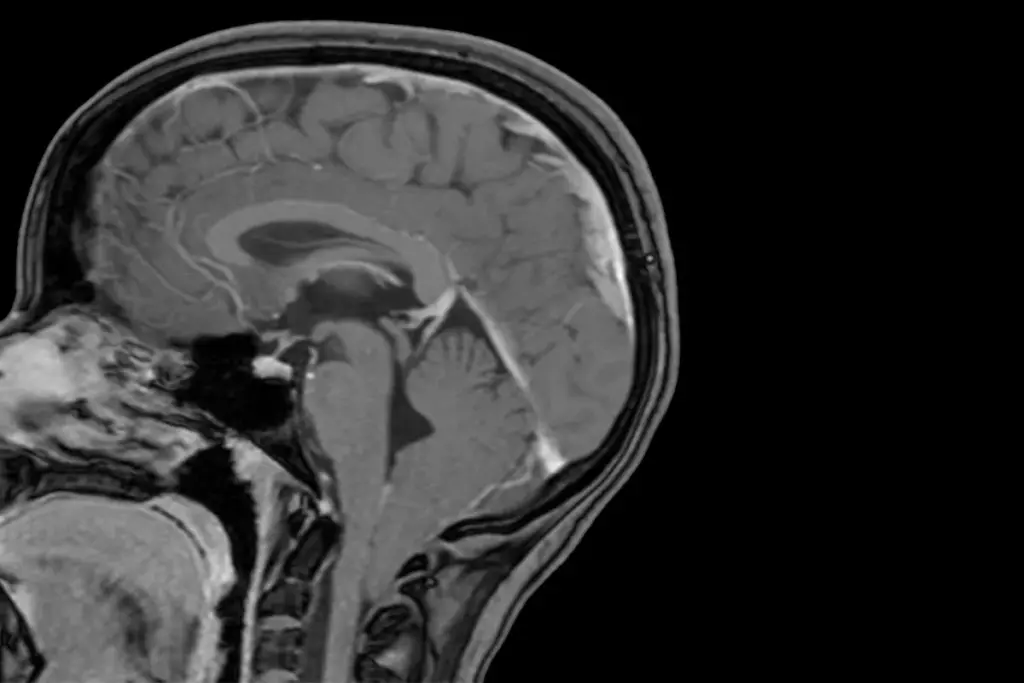

Diagnostic Procedures and Imaging

To diagnose Chiari malformation, doctors use a mix of clinical checks and imaging. MRI is the main tool, giving clear pictures of the brain and spinal cord.

MRI (Magnetic Resonance Imaging) |

Non-invasive imaging technique using magnetic fields |

Detailed images of brain and spinal cord structure |